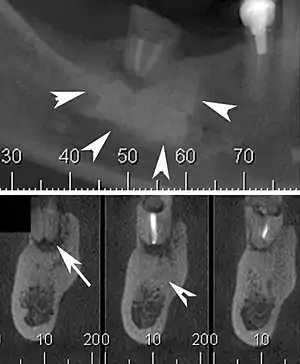

| Cone beam CT scan presenting a diffuse hyperdense lesion in the apex of a mandibular molar (arrowhead, top) adjacent to an inflammatory periapical lesion (arrow, bottom).[1] | |